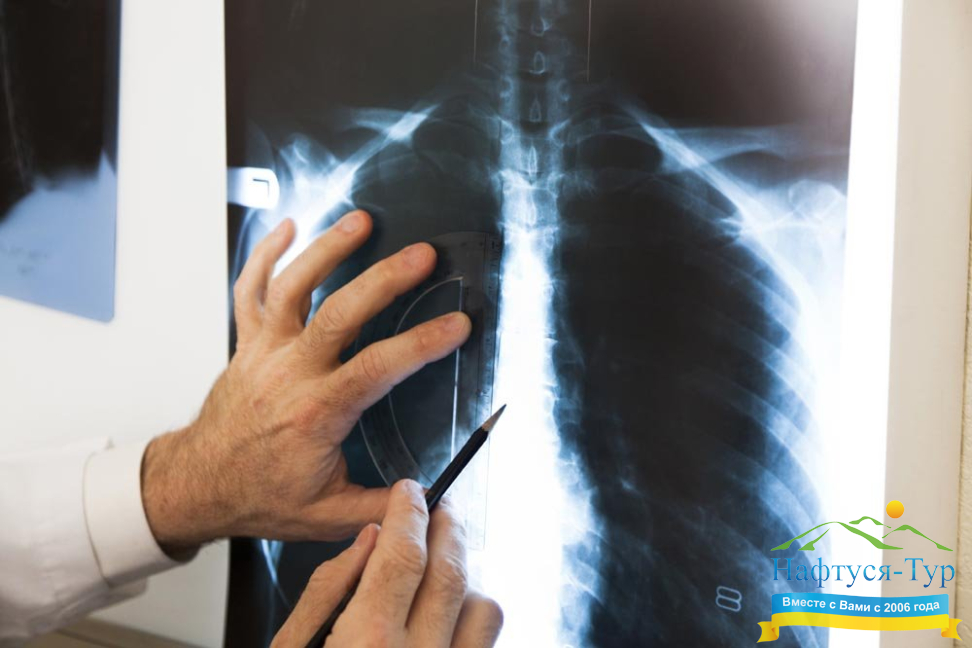

Строго говоря, Рентген – это фамилия ученого, который открыл электромагнитное излучение определенного диапазона, способного проникать через многие препятствия (например, проходить через тело человека), а затем засвечивать, оставлять изображение на фотопластинке. Благодаря этому такие диагностические методы, как рентгенография, рентгенологическое исследование, сегодня значатся в перечнях возможностей практически любого санатория и медицинского учреждения, а посетители данных заведений часто сокращают их официальное название до «Рентген». Рентгенологическое исследование является неинвазивным, оно подразумевает лишь строго дозированное вредное лучевое воздействие на человеческий организм. Данный вид диагностических исследований позволяет получить изображения внутренних органов, определить наличие в них патологий. Добавим, что рентгенография постоянно развивается, использование при диагностике компьютера позволяет получать значительно более широкий перечень информации, необходимой для определения и лечения недуга.